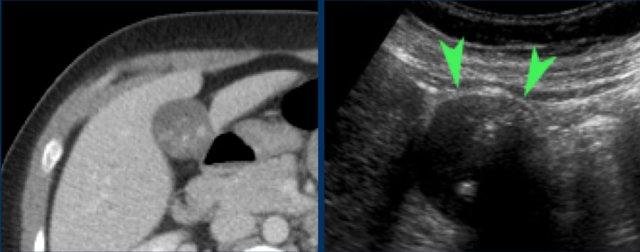

Ở bệnh nhân này, khám siêu âm ở tư thế nằm nghiêng không thể xác định được sỏi gây tắc nghẽn do sự hiện diện của nhiều viên sỏi.

Nếu siêu âm ở tư thế đứng cho thấy tất cả các viên sỏi di động đã di chuyển xuống đáy túi mật, bệnh nhân được yêu cầu nằm xuống trở lại, ngay lập tức xoay sang bên trái.

Bằng cách này, các viên sỏi sẽ ở lại vùng đáy túi mật, giúp quan sát rõ hơn cổ túi mật và ống túi mật (hình).

Tất cả các viên sỏi đã di chuyển về phía đáy túi mật, ngoại trừ viên sỏi kẹt (mũi tên).

Có hình ảnh dày thành túi mật, gợi ý viêm túi mật đang tiến triển (CRP là 110).